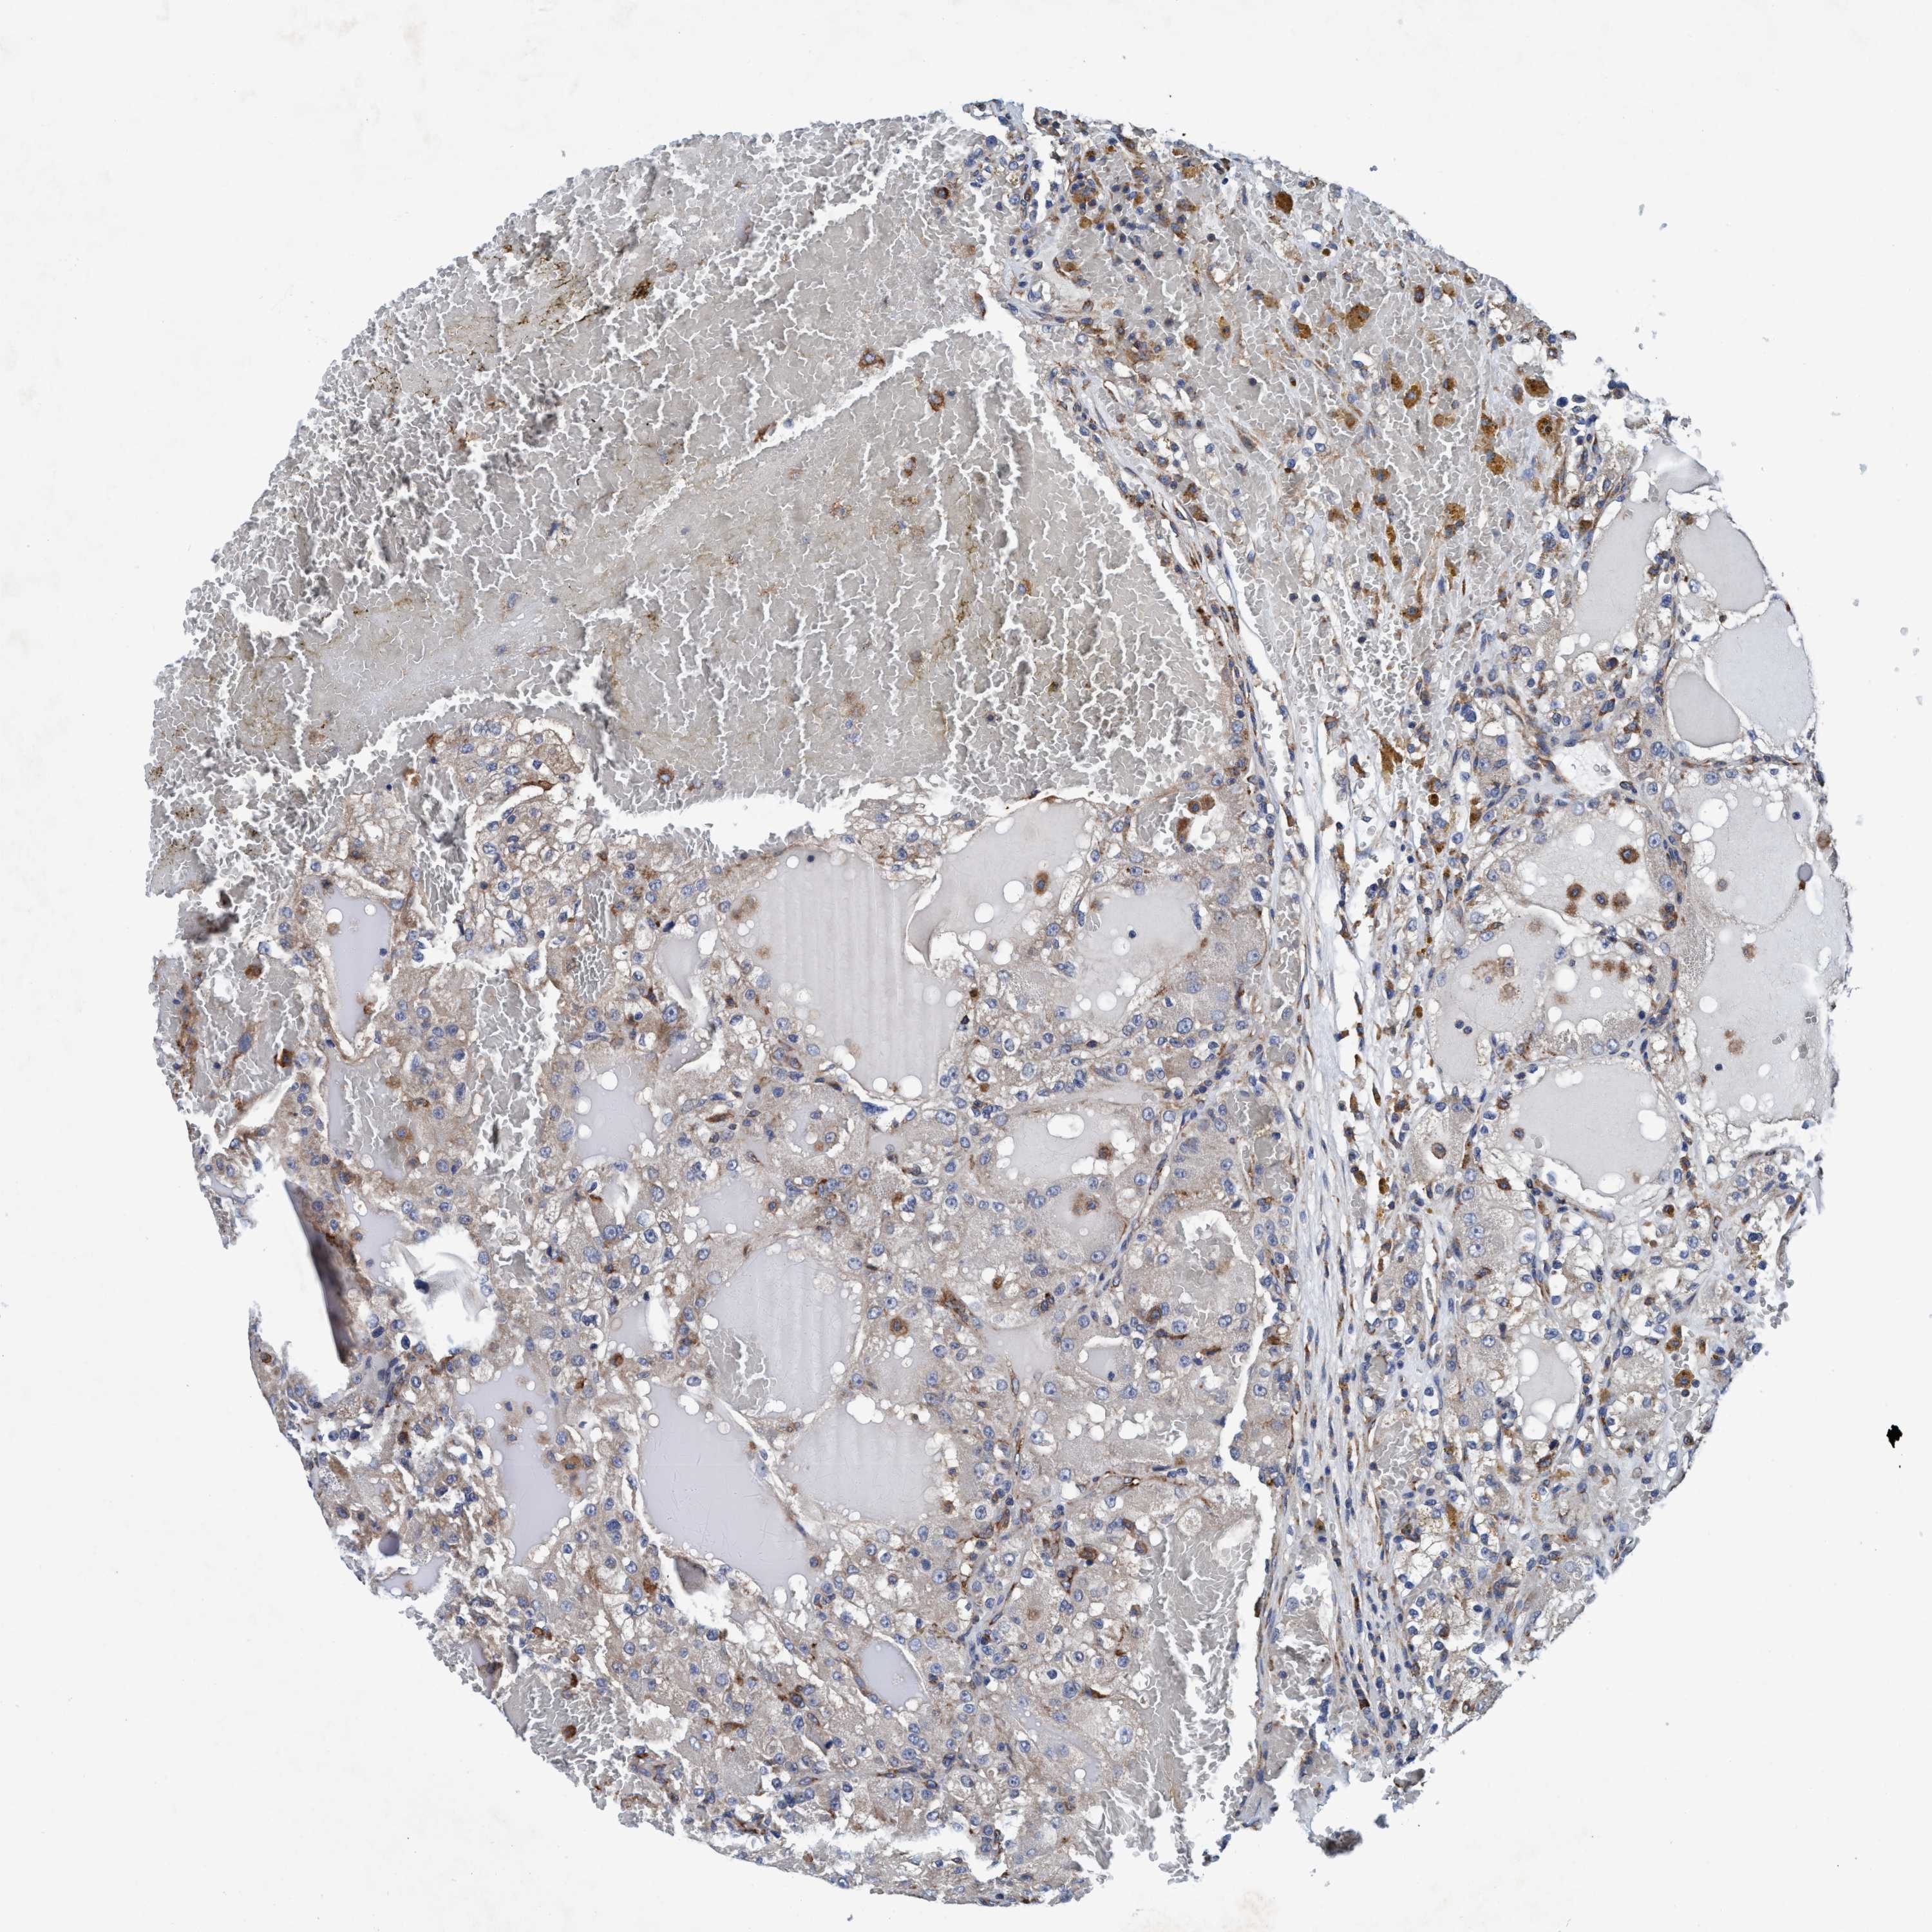

KIDNEY RENAL PAPILLARY CELL CARCINOMA (TCGA) - Interactive survival scatter ploti

ENDOG is potential prognostic, high expression is favorable in Kidney Renal Papillary Cell Carcinoma (TCGA)

Best expression cut offi